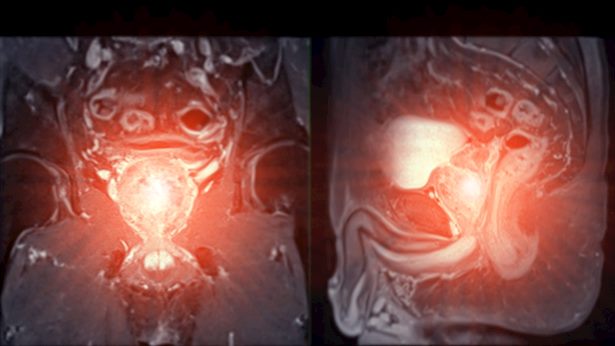

המחקר, אותו הוביל פרופ' דן ליבוביץ, מנהל המחלקה האורולוגית במרכז הרפואי קפלן מקבוצת כללית, בחן את הקשר בין נפח הערמונית של גברים לבין הסיכוי והחומרה של סרטן שהתגלה בביופסיה מוכוונת (מבוססת MRI). ממצאי המחקר, שפורסמו לאחרונה בכתב העת המדעי, Journal of Clinical Medicine, קוראים לבחון מחדש את שיטות האבחון הבינלאומיות המקובלות.

המחקר גילה כי סרטן הערמונית שכיח פי שניים יותר בגברים בעלי ערמוניות קטנות, בהשוואה לגברים עם ערמוניות גדולות. בנוסף, סרטן הערמונית שמאותר בערמוניות קטנות נוטה להיות חמור יותר (בעל דרגת ממאירות גבוהה יותר) מאשר סרטן המתגלה בערמוניות גדולות.

בנוסף, אחת המסקנות המשמעותיות ביותר נוגעת לסולם PIRADS, סולם הדירוג של ממצאים חשודים בערמונית המתגלים ב-MRI. המחקר מצא כי יכולת הניבוי של דירוג זה מושפעת משמעותית מנפח הערמונית. במטופלים עם ערמונית גדולה, הסבירות לאתר סרטן אגרסיבי בדרגות החשד הגבוהות (PIRADS 4-5) הייתה נמוכה יותר מאשר אצל מטופלים עם ערמונית קטנה.